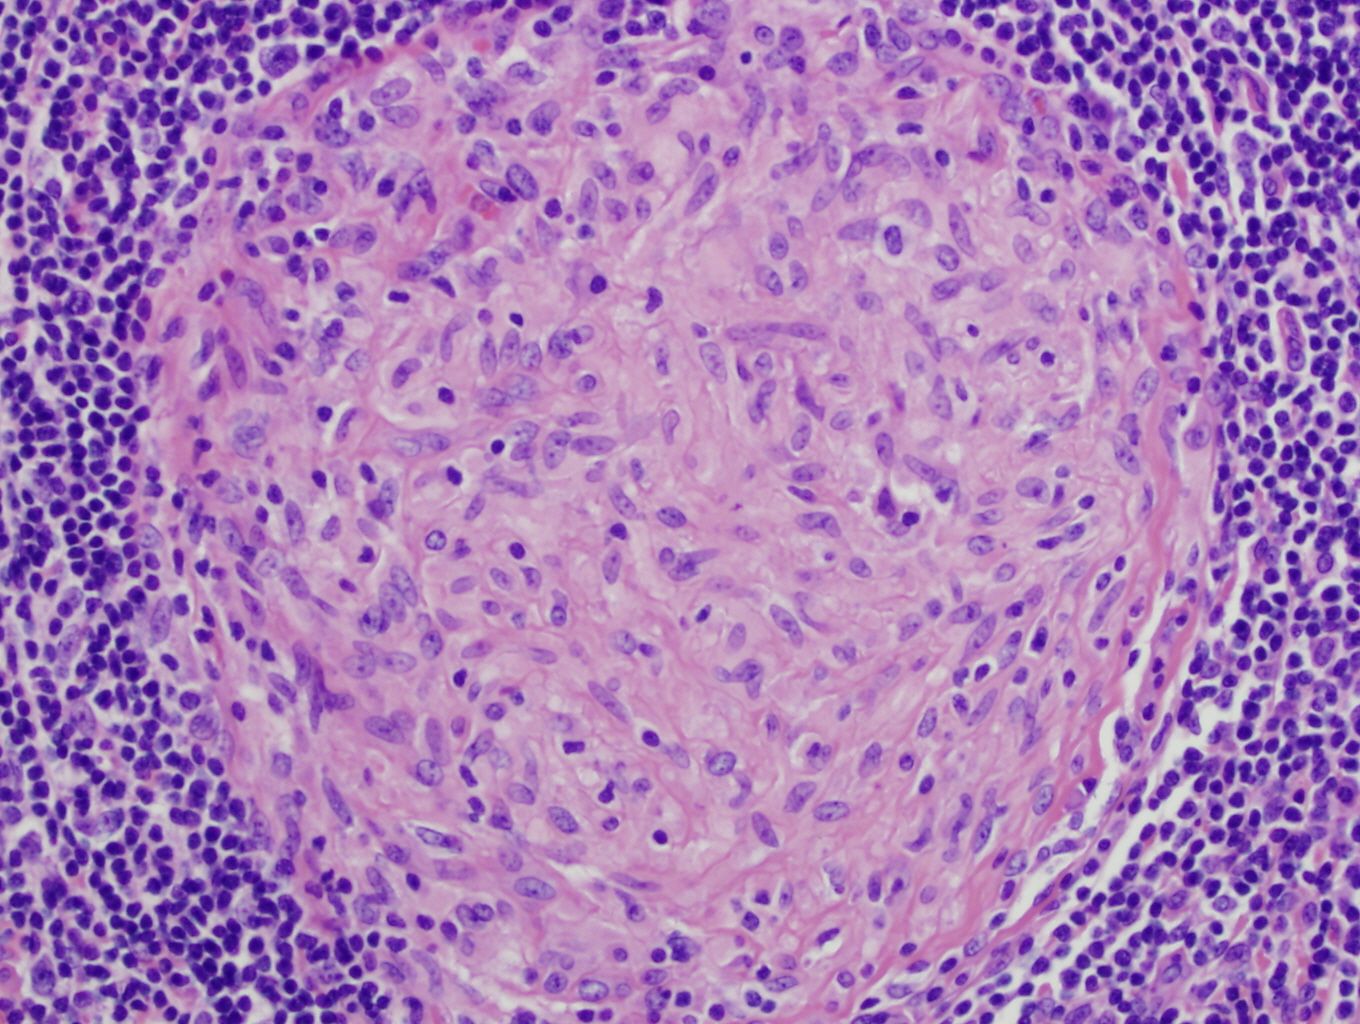

The most well-known method by which tuberculosis manipulates our immune system is through macrophages. They are the primary defense against invaders, the clean-up crew, and the primary tuberculosis target. The bacterium prefers to be engulfed by lung macrophages, which create a dense clump of cells that hides the bacterium for a long time, sometimes even years.